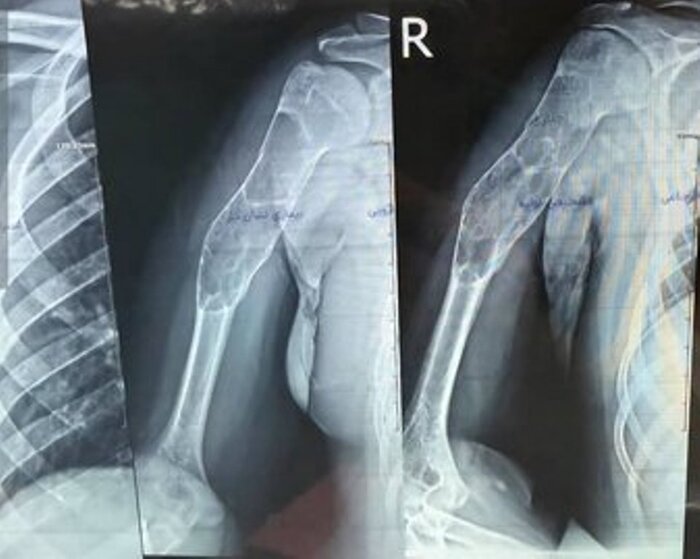

پارس‌آباد _ ایرنا _ عمل جراحی پیوند استخوان مصنوعی بازو به یک بیمار پسر ۱۶ ساله در پارس‌آباد مغان با موفقیت انجام شد.

مدیر شبکه بهداشت و درمان پارس‌آباد روز سه شنبه به خبرنگار ایرنا گفت: این عمل جراحی به رغم وجود توده کیستیک وسیع در بازوی این نوجوان، امروز توسط دکتر شهریار خوشبخت جراح و متخصص ارتوپدی و با همکاری تیم جراحی بیمارستان امام پارس‌آباد صورت گرفت.

دکتر شهریار خوشبخت، جراح و متخصص ارتوپدی هم درباره این عمل جراحی گفت: با توجه به وجود توده کیستیک وسیع در بازوی بیمار، تیم جراحی توانست به مدت سه ساعت پس از عملیات پلاک‌گذاری، توده وسیع را تخلیه و استخوان مصنوعی را جایگزین کند.

پیوند موفقت‌آمیز استخوان مصنوعی بازو در پارس‌آباد پیوند استخوان مصنوعی به بازوی بیمار

وی افزود: چنین اعمال پیچیده‌ای به طور معمول توسط فوق تخصص‌های جراحی دست در مراکز استان‌ها انجام می‌شود و خوشبختانه توانستیم برای اولین بار در شمال استان اردبیل در بیمارستان امام (ره) پارس‌آباد این عمل را با موفقیت انجام دهیم و اکنون بیمار با حال عمومی خوب بستری است و پس از چند روز مرخص خواهد شد.